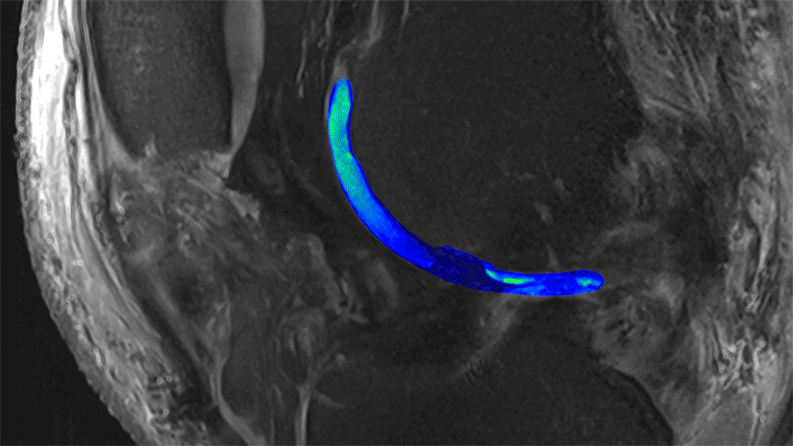

3-D videos reveal structural details of cartilage

3-D movies of cartilage reveal structural details, including damaged spaces. Sections shown here are cartilage along the femur, or thigh bone. Image credit: Didier Laurent and Aparna Srikanth